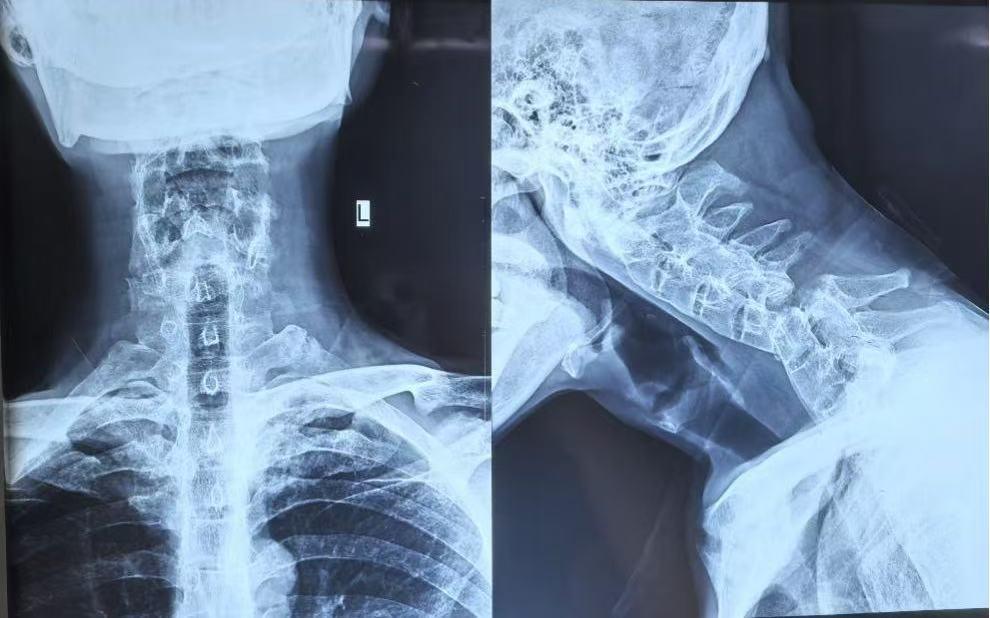

患者是一位中年男性,罹患强直性脊柱炎多年,整个脊柱融合僵直,如同一根“脆弱的竹竿”。一次意外不慎跌倒,颈椎多处骨折并严重脱位,错位的椎体将最脆弱的脊髓神经挤压到极限,生命悬于一线。“就像一根即将被扯断的电线。”主刀医生闫铭副主任医师形容道。

对普通人而言,颈椎骨折属于高风险损伤,手术难度不言而喻。而该患者脊柱僵硬,还伴有严重骨质疏松,所需植入螺钉时,如同在“酥饼上雕刻”,稍有不慎就会失败。更棘手的是,长期病变让正常的解剖结构完全混乱,医生手术视野中失去了所有熟悉“路标”。每一次操作都如同在雷区中穿行,随时可能损伤血管和神经,造成灾难性后果。

经过1个半小时的精心施术,随着最后一道缝合完成,手术宣告成功。手术室里紧张凝重的气氛,终于得以缓解。术后X光片显示,内固定位置准确,颈椎序列得到理想恢复。